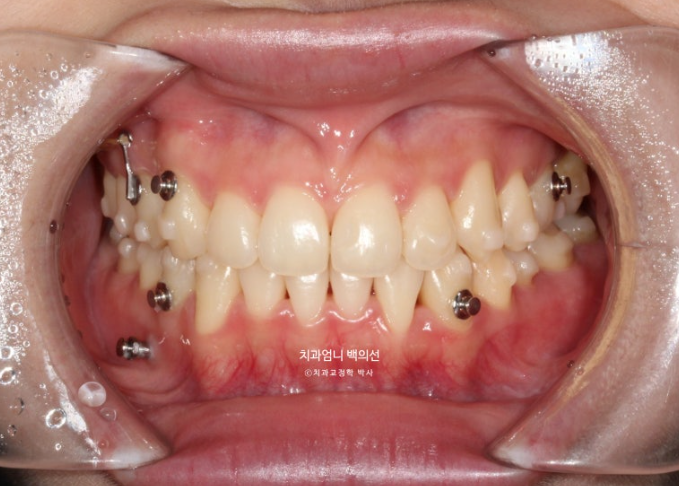

중간평가입니다.

필요한 곳에 교정용 나사인 미니스크류를 심고 진행해야 효율이 좋습니다.

24.09

중심선이 처음에 비해 좋아졌으나 아직 불일치가 보입니다.

환자가 직접 뺏다꼈다 하는 고무줄 처방도 들어갔고 첫번째 세트와 70개 장치를 모두 낀 후 모습은 다음과 같습니다.